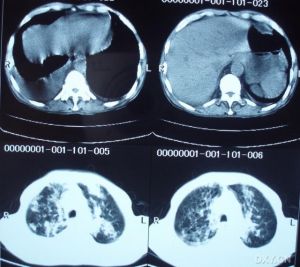

為了查清痰多的病因,應到醫院詳細檢查,如拍x線胸部照片。可疑肺癌時,應照斷層片或胸部cT檢查,驗痰查,找癌細胞,最好做氣管鏡檢查,以便早確診、早手術、早放療或化療。如果是感染,應做痰培養檢查。培養出致病菌後,還需做藥物對該菌的敏感試驗,以便有針對性的使用抗生素。